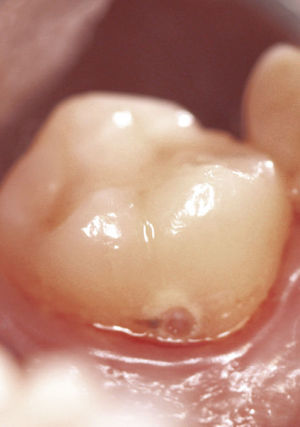

Se puede observar una tinción de color rojizo de la corona dentaria en las localizaciones muy hacia coronal y el defecto primario se puede sondar (fig. 10). Con frecuencia, los dientes afectados ofrecen un aspecto externo in- tacto, pero muestran una puerta de entrada situada en la zona proximal-cervical. El proceso evoluciona de forma asintomática y el diagnóstico suele ser un hallazgo radiográfico casual (figs. 9 y 11). La prueba de sensibilidad suele ser positiva y la prueba de percusión es negativa. Hay que hacer el diagnóstico diferencial con reabsorciones internas o externas y, en caso de defectos cervicales localizados, con una caries radicular.

Características radiográficasLas reabsorciones cervicales invasivas se caracterizan por los signos radiográficos siguientes:

- •

Origen en el límite amelocementario.

Línea radioopaca alrededor de la luz del conducto (predentina).

Aspecto marmóreo del defecto.

Forma perimetral errática.

Orientación longitudinal.

Espacio periodontal continuo.